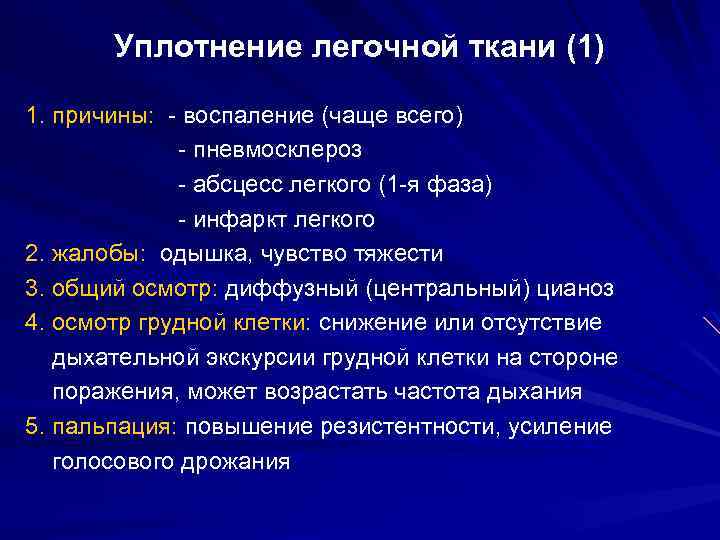

Острая внебольничная пневмония по МКБ-10: признаки и примеры